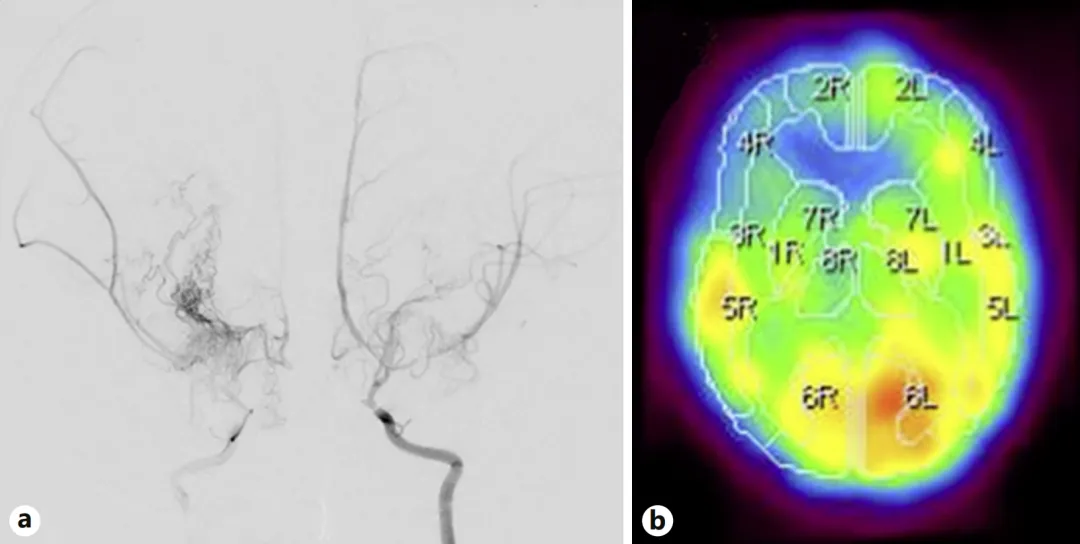

患儿最初的症状较为隐蔽:表现为突然摔倒,随后出现突发性抽搐。家长紧急送医后,检查结果令人担忧——确诊为烟雾病,同时合并脑梗死,双侧颈内动脉呈现严重狭窄,右额叶脑血流明显减少。

图a:如同大脑的三条“主要供血通道”同时发生堵塞,脑组织长期处于“缺氧”边缘,随时可能面临危险;

图b:这也解释了患儿反复发生猝倒的原因——当大脑急性缺血时,身体会突然失去力量,无法维持平衡。